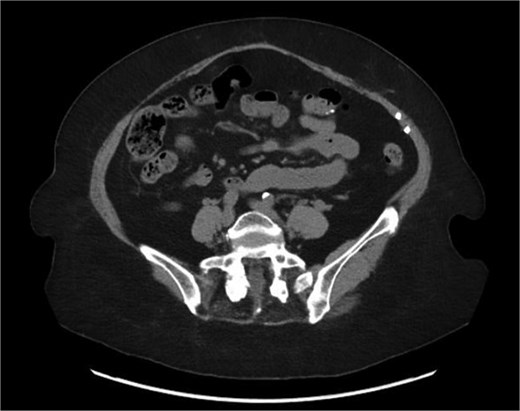

Postoperatively, the patient had an uneventful course and was discharged on Day 5. At the 6-month follow-up, she remained asymptomatic. A CT scan performed at her request for reassurance showed no signs of recurrence or acute abdominal pathology (Figs 4 and 5).

Sagittal section of CT abdomen and pelvis 6 months after the surgery.